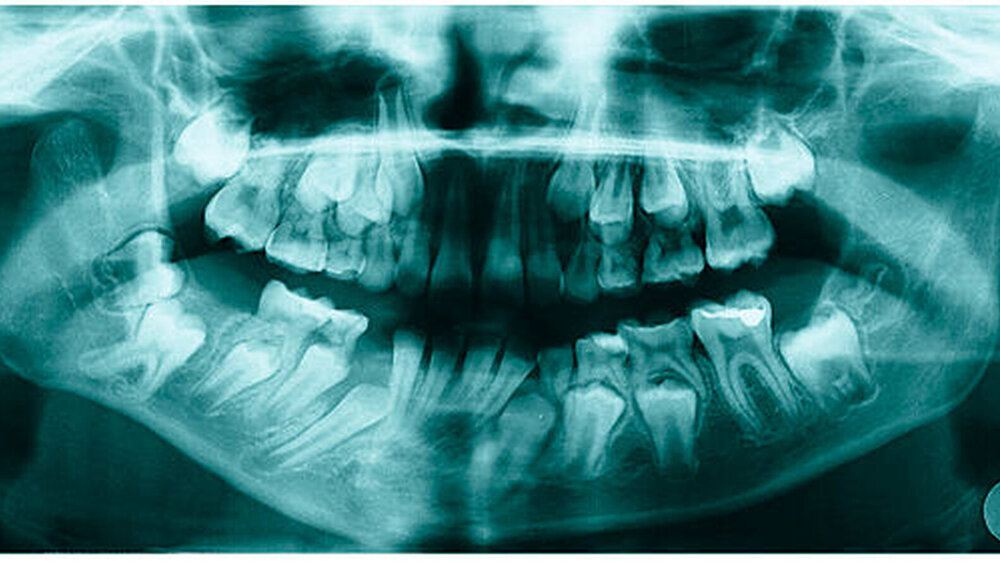

Bereits 2004 wies Carla Evans [Evans, 2005] auf das Risikomanagement bei Allgemeinerkrankungen hin und stellte am Beispiel der JIA dar, dass Unterkieferrücklagen und frontal offene Bisse aus der Kiefergelenkzerstörung entstehen können. Die Röntgenaufnahmen einer JIA-Patientin mit oligoartikulärer Form und Beteiligung des rechten Kiefergelenkes zeigen den typischen Verlauf sehr gut. Bei ursprünglich sehr dezenten Befunden, wie einer s-förmigen Mundöffnung von 44 mm, einer geringen Mittenabweichung um 2 mm nach rechts und einem frontal offenem Biss klagte sie über Schmerzen beim Essen, was den Anlass zur weiteren Diagnostik bot. Die erste Panoramaröntgenschichtaufnahme (Abbildung 1a-c) zeigt auf der rechten Seite einen abgeflachten Kondylus und eine bereits verstrichene Fossa condylaris. Ein Jahr später vermittelt das Fernröntgenseitenbild (Abbildung 1d) trotz fortschreitender kondylärer Resorption ein harmonisches Bild, während nach drei Jahren bei voranschreitendem Abbau des rechten Kondylus (Abbildung 1e) eine Rücklage der Mandibula und eine Bissöffnung manifest sind (Abbildung 1f).

Mithilfe der Panoramaröntgenschichtaufnahme lässt sich in bis zu 67 Prozent der Fälle bereits eine Kiefergelenkdestruktion bei Kindern mit JIA feststellen [Küseler et al., 1998; Twilt et al., 2004; Abramowicz et al., 2014]. Eigene Untersuchungen bestätigten die Eignung als Screening-Verfahren [Mäckelmann, 2008].

Bei 152 durchschnittlich 12-jährigen Rheumapatienten wurden die kondyläre Morphologie und Symmetrie beziehungsweise Asymmetrie im Vergleich zu einer Kontrollgruppe anhand der OPG analysiert. Zur Analyse erfolgte die Zuordnung zu vier morphologischen Graden je Kondylus (Abbildung 3a-d). Bei 45 Prozent der Rheumapatienten waren morphologische Veränderungen im Rahmen kondylärer Resorption unterschiedlicher Ausprägung zu finden. Die „Kontrollpatienten“ ohne JIA zeigten nur zu 14 Prozent formatypische Kondylen. Der Unterschied zwischen den beiden Gruppen war signifikant. Daher sollte bei der Routineauswertung von Panoramaröntgenschichtaufnahmen auf diese Anzeichen geachtet werden, insbesondere auch unter dem Aspekt, dass laut Assaf [2011] durchschnittlich 4,3 Jahre zwischen Erstmanifestation der JIA und Erstvorstellung in der Rheumasprechstunde des UKE liegen.